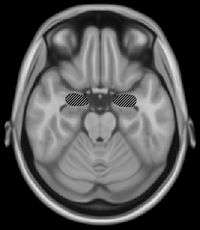

The basal ganglia are a group of nuclei which are located in the medial temporal lobe, above the thalamus and connected to the cerebral cortex. Specifically, the basal ganglia includes the subthalamic nucleus, substantia nigra, the globus pallidus, the ventral striatum and the dorsal striatum, which consists of the putamen and the caudate nucleus.[8] The basic functions of these nuclei deal with cognition, learning, and motor control and activities. The basal ganglia are also associated with learning, memory, and unconscious memory processes, such as motor skills and implicit memory.[4] Particularly, one division within the ventral striatum, the nucleus accumbens core, is involved in the consolidation, retrieval and reconsolidation of drug memory.[9]